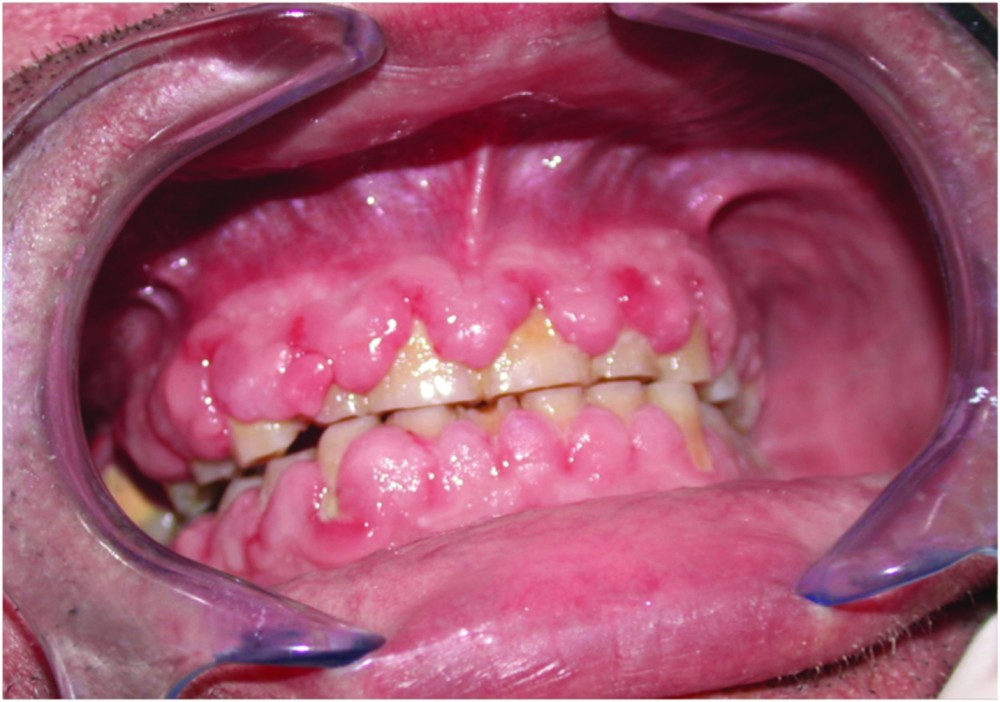

Examen clinique. La gencive était hypertrophique. Elle formait des nodules fibreux, sessiles, ayant tendance à confluer, et plutôt pédiculés dans la région des papilles. La gencive marginale était associée à de la plaque dentaire.

Histoire de la maladie. Depuis trois ans, le patient présentait une hypertrophie gingivale qui recouvrait en partie la face vestibulaire des dents.